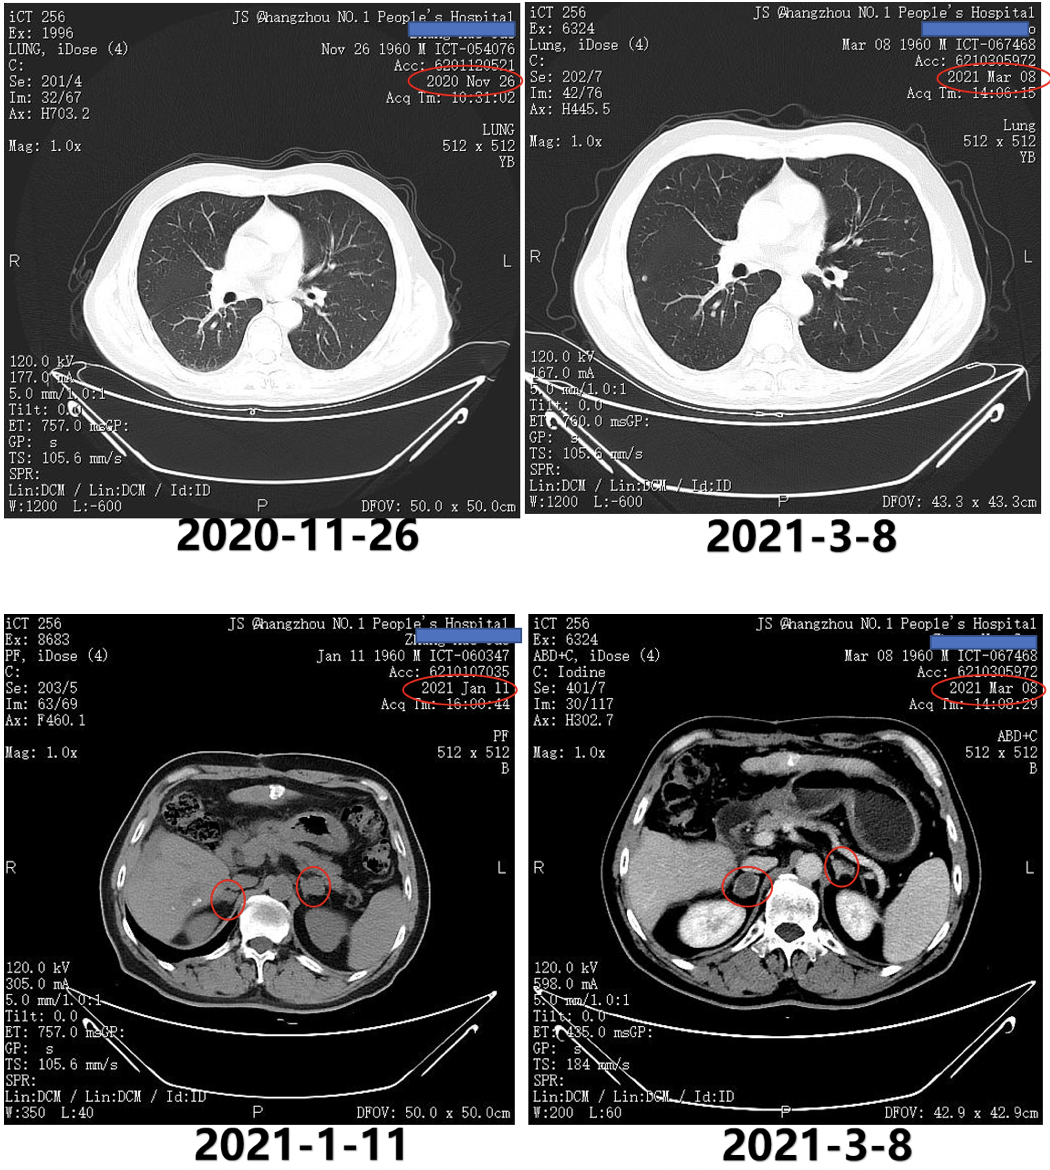

2020年12月2日即第1次TACE术后5天复查AFP为156.3ng/ml。2021年1月11日腹部CT提示,左侧肾上腺病灶较2020年11月26日明显增大,考虑转移(图3);2021年1月11日AFP明显升高为303.4ng/ml。

图3.2020年11月26日与2021年1月11日CT

2021年3月8日复查AFP为>1210ng/ml;2021年3月8日复查CT提示,双肺转移双侧肾上腺转移;左侧肾上腺较前变小,但右侧肾上腺明显增大;右侧髂骨转移(图5)。

图5.2021年3月8日复查CT